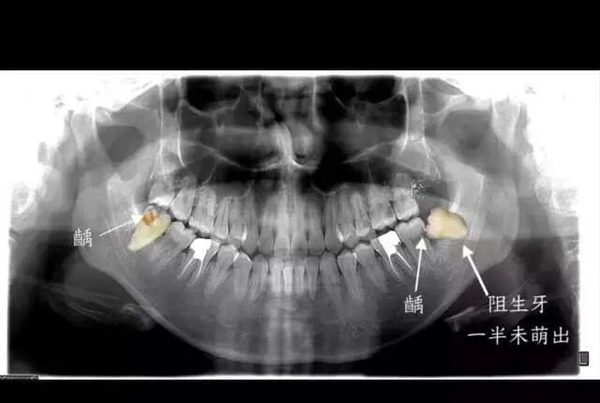

但是,如果拔一颗水平阻生牙的话,那创伤就可能很大,拔一颗恐怕要耗上半个多小时,耗尽医生的精力的同时,病人也可能累得张不开嘴。

智齿前方的牙齿已经出现了蛀洞,即龋病,图中可见一颗阻生牙。图源:作者